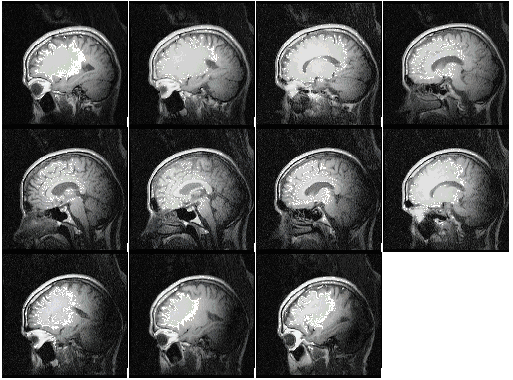

Sagittal Sections